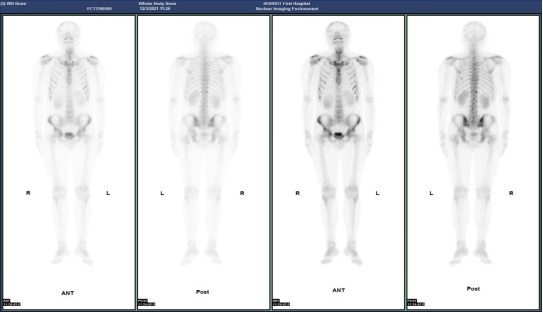

(病例一)患者,男,39岁,右肺门中央型肺癌T3N2MX(IIIB期),为明确是否有骨转移来我科就诊。MIP图示:额骨右侧、C6、T12、左侧第6肋,右侧第7、8肋多发小片状放射性摄取增高灶,SPECT/CT融合图示:额骨右侧、C6、T12、左侧第6肋,右侧第7、8肋未见明显骨质破坏。结合肺癌病史,考虑额骨右侧、C6、T12、左侧第6肋,右侧第7、8肋多发骨转移。如下图: